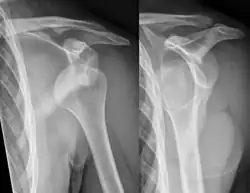

X-ray at left shows anterior dislocation in a young man. X-ray at right shows the same shoulder after reduction and internal rotation, revealing a Bankart lesion and a Hill-Sachs lesion.

In over 95% of shoulder dislocations, the humerus is displaced anteriorly.[8] In most of those, the head of the humerus comes to rest under the coracoid process, referred to as sub-coracoid dislocation. Sub-glenoid, subclavicular, and, very rarely, intrathoracic or retroperitoneal dislocations may also occur.[9]

A Hill–Sachs lesion is an impaction of the head of the humerus left by the glenoid rim during dislocation.[6] Hill-Sachs deformities occur in 35–40% of anterior dislocations. They can be seen on a front-facing X-ray when the arm is in internal rotation.[11] Bankart lesions are disruptions of the glenoid labrum with or without an avulsion of bone fragment.[12]